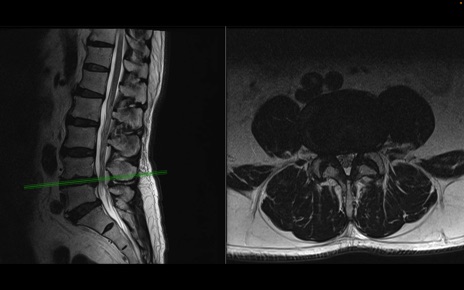

【整形】TIPS症例2 腰椎MRI 横断像と矢状断像

【症例】70歳代男性

【主訴】左下肢痛

【現病歴】2週間前くらいから腰痛、左下肢痛あり。左臀部から大腿、下腿外側のしびれが常時ある。歩行とともに同部位の痛みあり。

【身体所見】Lasegue70-/60+、Bragard-/±、PTR ±/±、ATR -/-、IP 5/5、TA 5/4、TS 5/5、EHL 右第1足趾なし/3、FHL 5/5、hypersthesia(-)、足背動脈触知良好

異常所見と診断は?